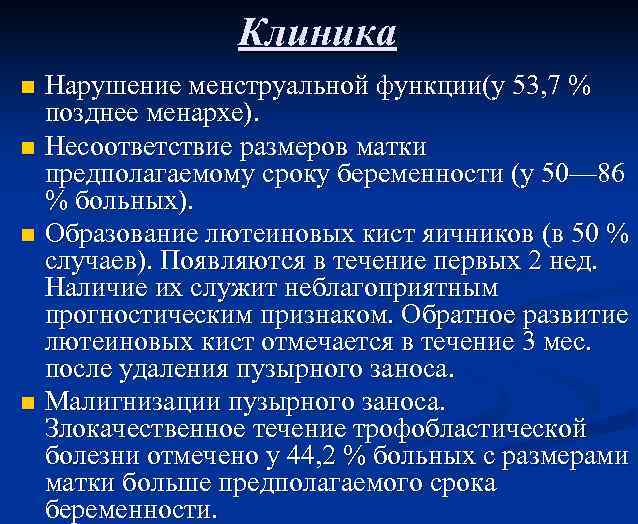

Клиника n n Нарушение менструальной функции(у 53, 7 % позднее менархе). Несоответствие размеров матки предполагаемому сроку беременности (у 50— 86 % больных). Образование лютеиновых кист яичников (в 50 % случаев). Появляются в течение первых 2 нед. Наличие их служит неблагоприятным прогностическим признаком. Обратное развитие лютеиновых кист отмечается в течение 3 мес. после удаления пузырного заноса. Малигнизации пузырного заноса. Злокачественное течение трофобластической болезни отмечено у 44, 2 % больных с размерами матки больше предполагаемого срока беременности.